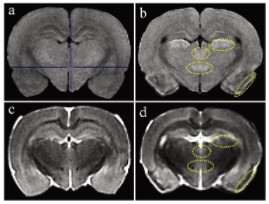

圖1顯示了T1和T2加權(quán)MRI圖像。與對照組相比, 匹羅卡品處理的動物在梨狀皮質(zhì)、丘腦外側(cè)核、丘腦室周后核和大腦下丘腦后核的T1加權(quán)圖像顯示出高T1信號(圖1a和b)。在匹羅卡品處理的動物的T2加權(quán)圖像中,與對照組相比,在梨狀皮質(zhì)觀察到低T2信號,對應(yīng)于高T1信號區(qū)(圖1c和d)。其他3個高T1信號區(qū)的T2信號強(qiáng)度與對照組相當(dāng)(中等強(qiáng)度)(圖1c和d)。

當(dāng)前易于使用的緊湊型小動物磁共振成像系統(tǒng)在匹羅卡品誘導(dǎo)的大鼠腦損傷的臨床前毒理學(xué)病理檢查中的適用性。高T1和低T2信號顯示明顯的組織病理學(xué)神經(jīng)元損傷,盡管組織病理學(xué)檢查更為敏感。